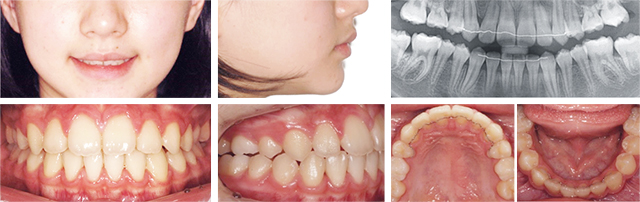

앞니가 벌어져 있고 전방으로 뻐드러져 보여 개선을 위해 내원. 검진 결과 다수의 영구치가 결손 되어 있고 유치가 남아있으며 위턱에 비해 아래턱이 상대적으로 후방에 위치한 상태로 진단되어 Bionator를 이용한 1차 교정치료를 통해 아래턱의 위치를 개선시키고 2차 치열 교정을 통해 유치를 발치 하지 않고 함께 이동하여 종료하였습니다.

2단계로 나누어 진행한 치료이며 성장기 청소년의 골격 부조화를 가철식 장치를 이용하여 개선 후 치아의 정교한 이동을 위해 일반적인 브라켓 장치를 부착하여 배열하였습니다. 기준에 비해 후퇴되어 있던 아래턱의 위치가 전방 이동되었으며, 양호한 배열 상태와 교합 관계를 획득하였습니다.